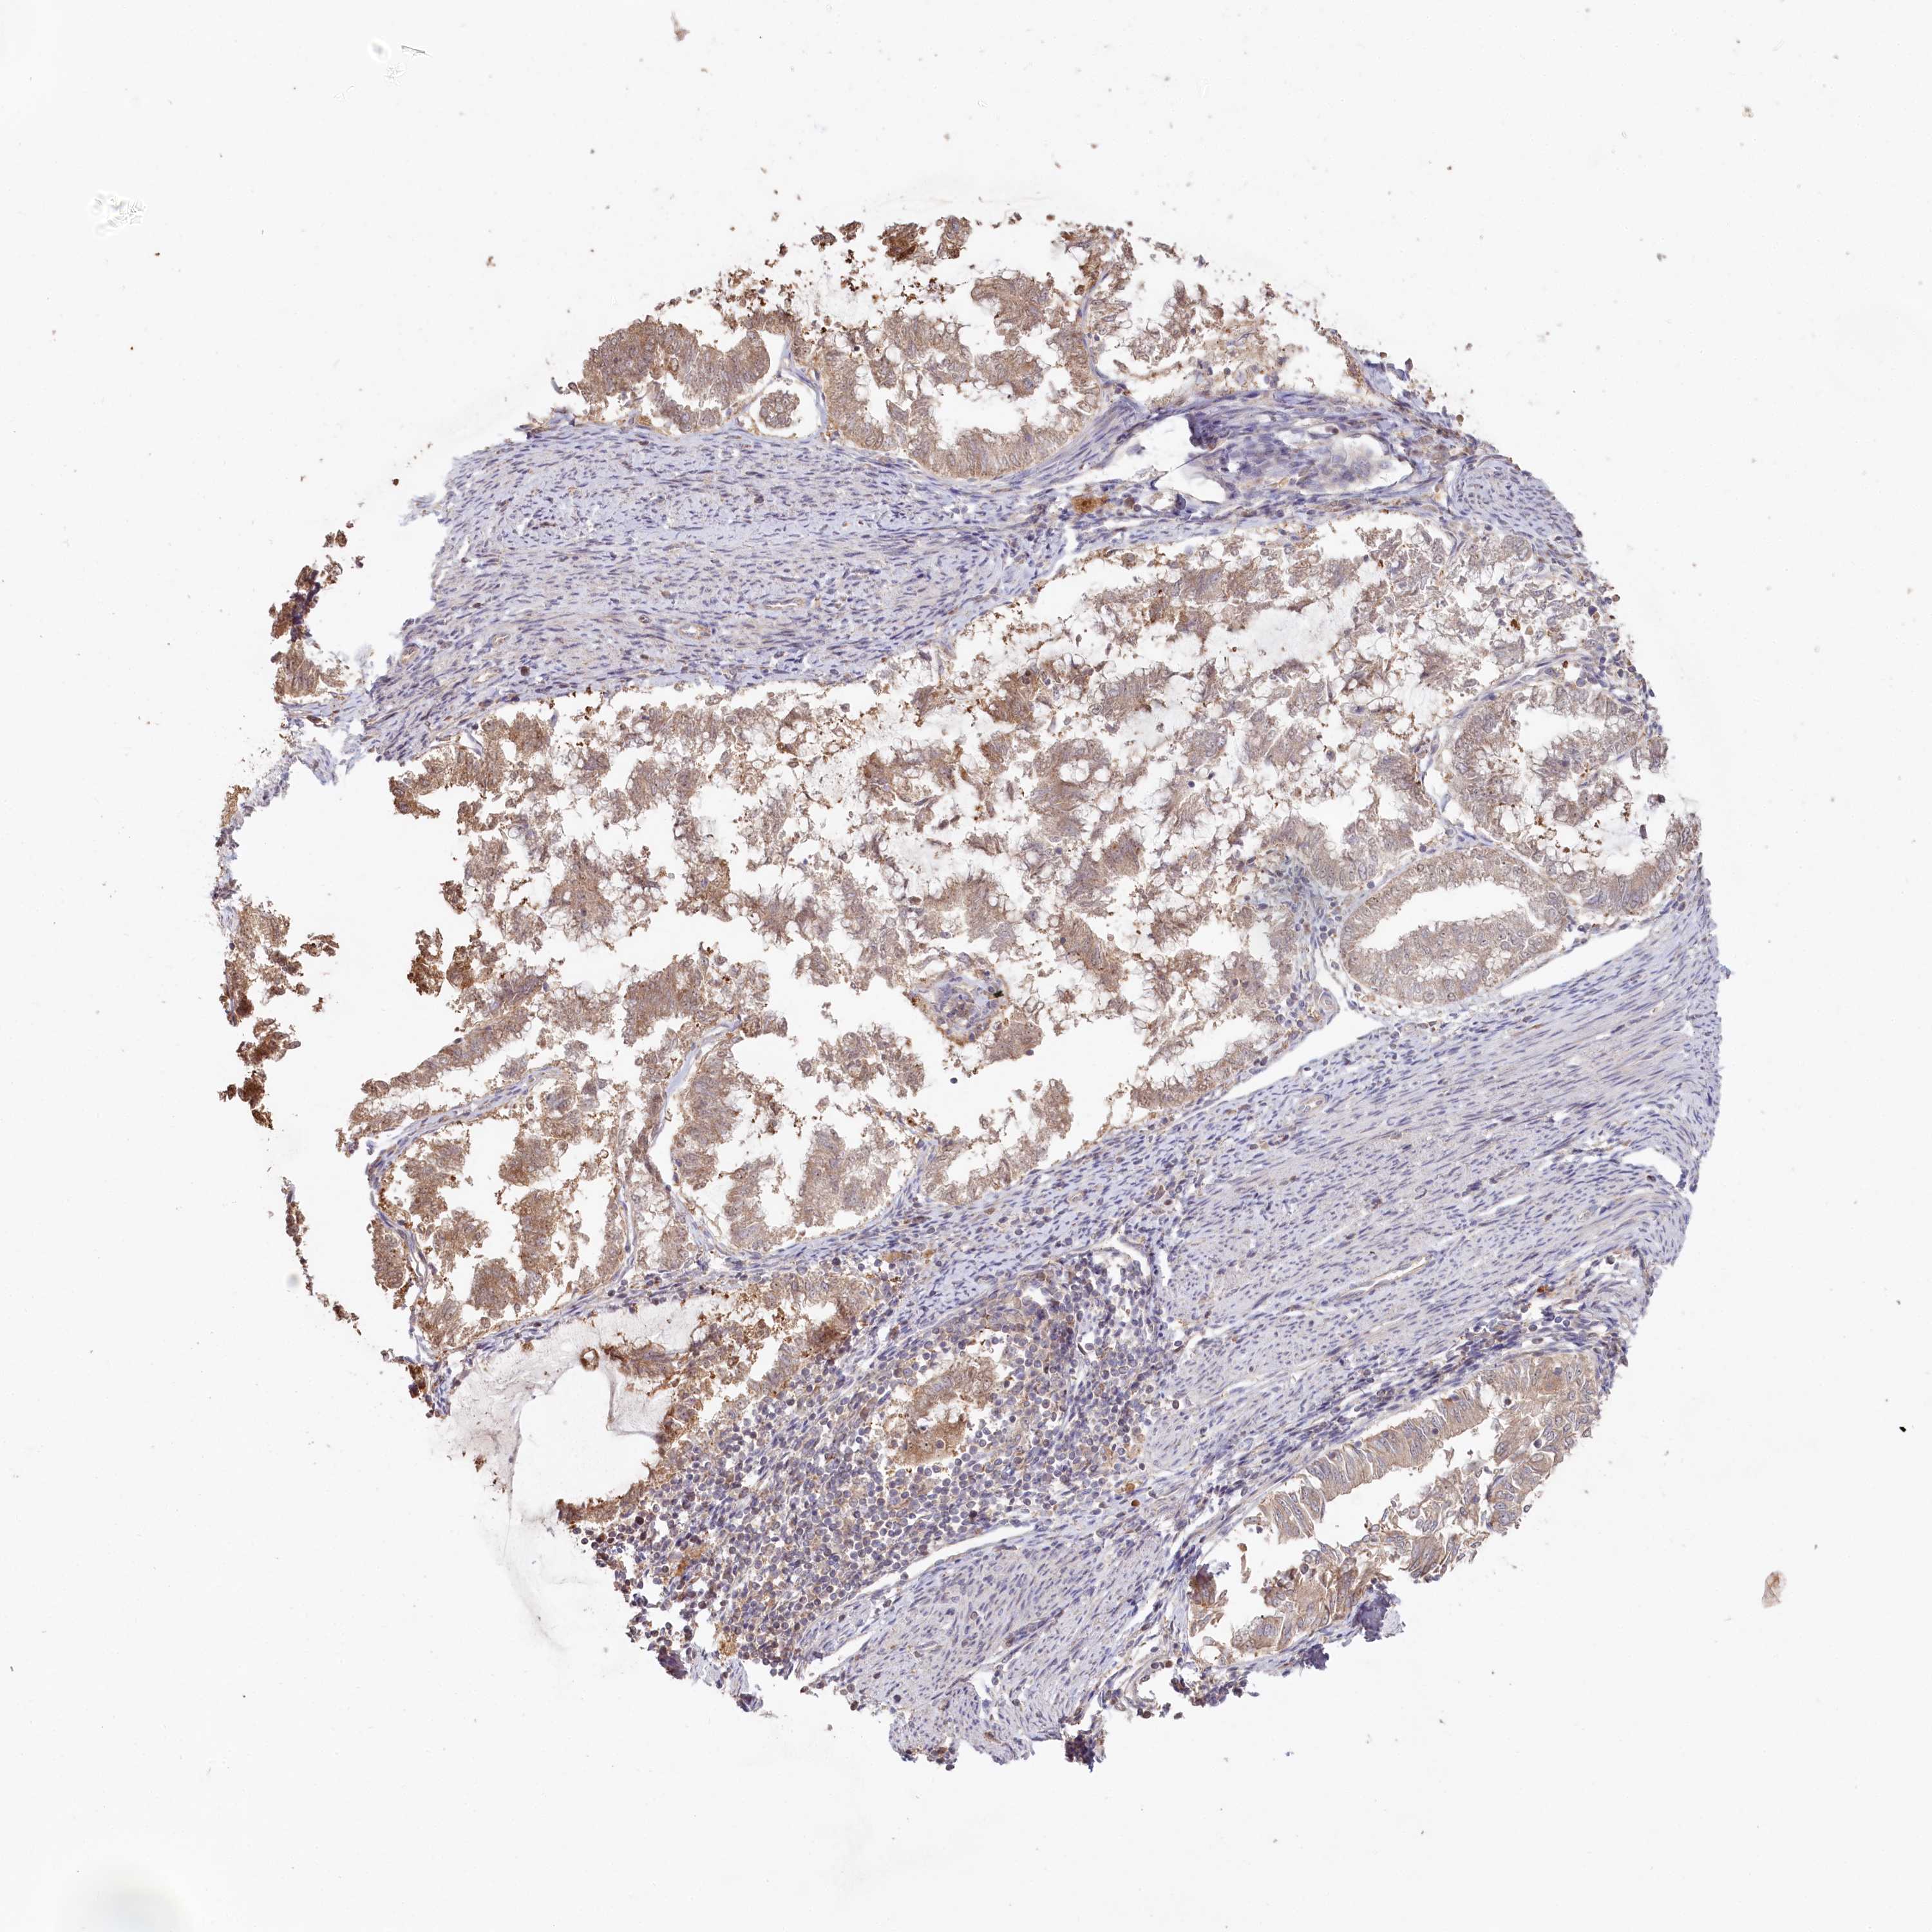

ENDOMETRIAL CANCER - Protein expressioni

A mouse-over function shows sample information and annotation data. Click on an image to view it in a full screen mode. Samples can be filtered based on level of antibody staining by selecting one or several of the following categories: high, medium, low and not detected. The assay and annotation is described here.

Note that samples used for immunohistochemistry by the Human Protein Atlas do not correspond to samples in the TCGA dataset.

Antibody stainingi

Antibody staining in the annotated cell types in the current human tissue is reported as not detected, low, medium, or high, based on conventional immunohistochemistry profiling in selected tissues. This score is based on the combination of the staining intensity and fraction of stained cells.

Each image is clickable and will lead to virtual microscopy that enables deeper exploration of all samples and also displays staining intensity scores, fraction scores and subcellular localization as well as patient and tissue information for each sample.

Antibody HPA038547

Antibody HPA038548

Staining

High

Medium

Low

Not detected

Intensity

Strong

Moderate

Weak

Negative

Quantity

>75%

75%-25%

<25%

None

Location

Nuclear

Cytoplasmic/membranous

Cytoplasmic/membranous,nuclear

Adenocarcinoma, metastatic, NOS